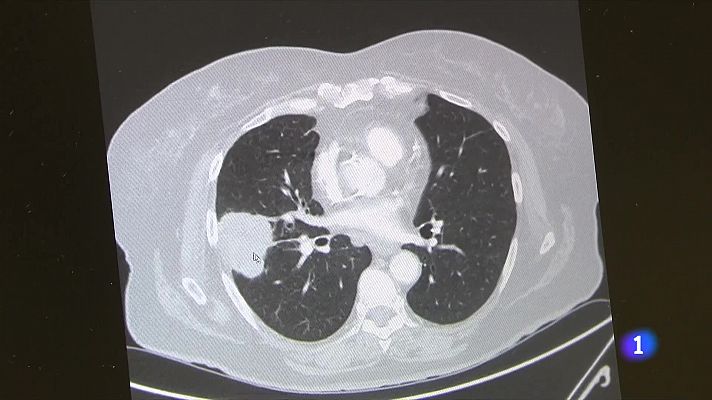

El càncer del pulmó és el segon en mortalitat entre les dones i el tercer en incidència en homes. Aquest tumor és un dels més indicats per aplicar el que s'anomena medicina de precisió, és a dir, el desenvolupament de tractaments personalitzats en funció de les característiques genètiques dels pacients.